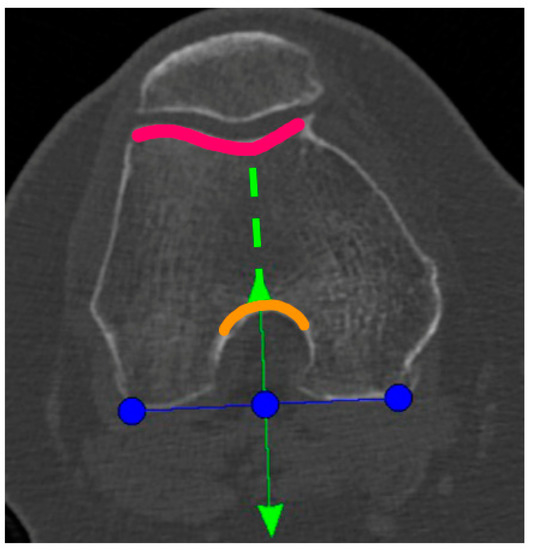

In the definite implant planning, the tibia component was set to 0° compared to this femur-based rotation landmark (Figure 2). Then, tibia component size was determined and the tibia rotation was fine-tuned to avoid component over- or under-hang (Figure 3a,b). The other alignment parameters were set to reconstruct the natural slope up to 7° maximum and the joint-line obliquity up to 3° varus. The proudness of the implant was pre-set at 4 mm.

Figure 3.

TRA is 1° (a) and 4° (b) externally rotated to the femur-based rotation landmark.